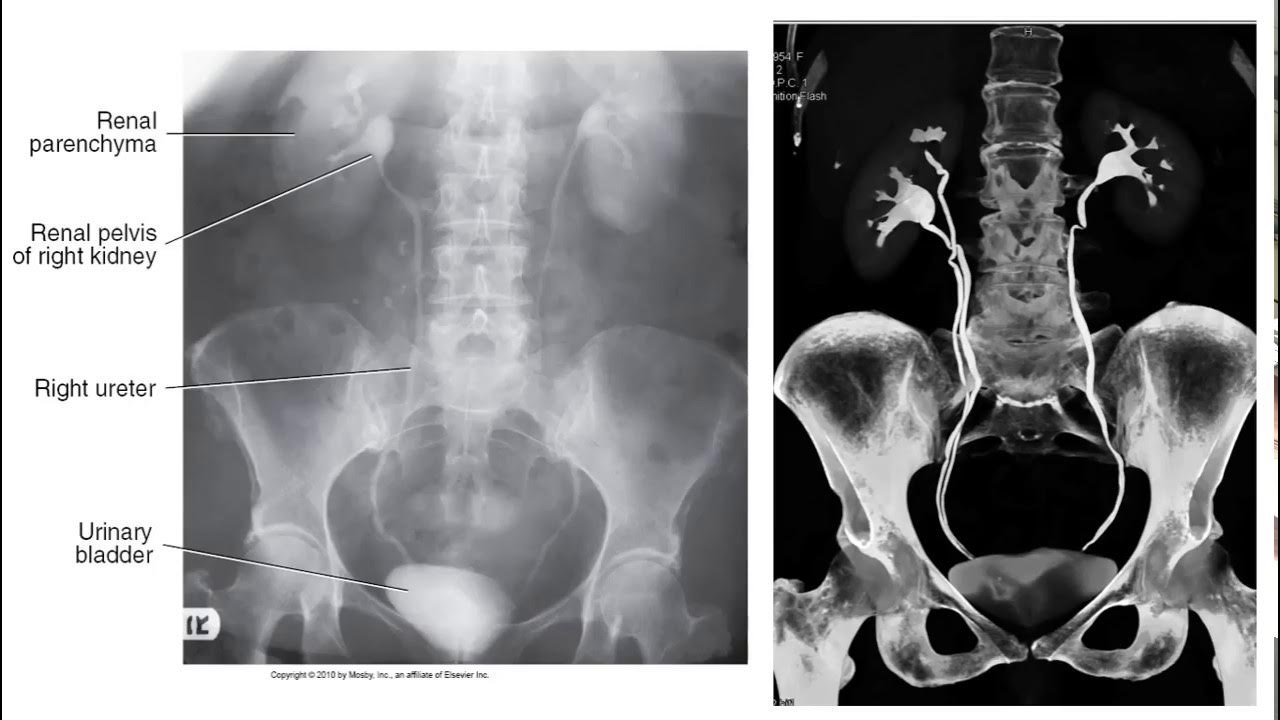

- 😀 Contrast travels from veins → right heart → lungs → left heart → aorta → target organs; this pathway determines imaging timing.

- 😀 Different organs require imaging at specific contrast phases: early arterial, late arterial, portal venous, nephrogenic, and excretory phases.